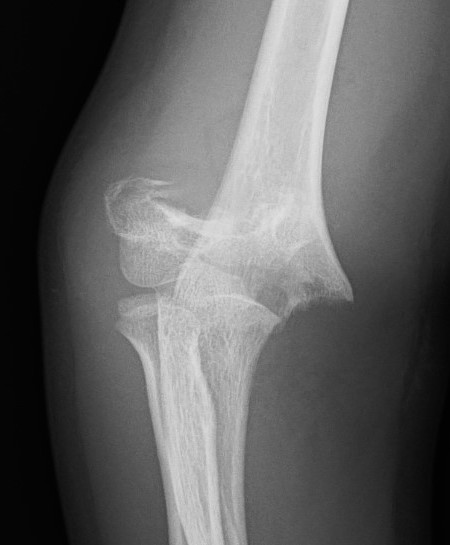

Lateral Xray

Position for good lateral

- thumb vertical

- hand above elbow

Anterior angulation

- shaft - condylar axis

- normally 40o

Lines

Anterior humeral line (AHL)

- should pass through middle of capitellum

Radio-capitellar line

- pass through capitellum

Teardrop

- shadow above the capitellum

- anterior dense line: posterior margin of the coronoid fossa

- posterior dense line: anterior margin of the olecranon fossa

- inferior portion: ossification center of the capitellum

AP X-ray

Baumann's Angle

Technique

- angle between longitudinal axis humerus and capitellar physis

- should equal uninjured side

- 75o normal

Cubitus varus

- varus malposition > 81°

Cubitus valgus

- < 70o